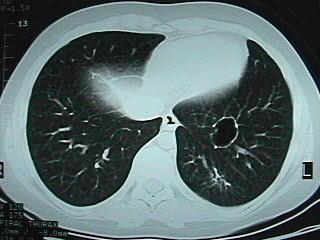

La tomografía axial computada (TAC) de tórax mostró

imágenes nodulares en ambos campos pulmonares,

cavitadas, de paredes gruesas, con estructuras

bronquiales interiores

(Fig. 3). Ingresa

Figura 3:

TAC de tórax, base

izquierda. Nódulo central y otro cavitado contra

parrilla

en cara posterior.